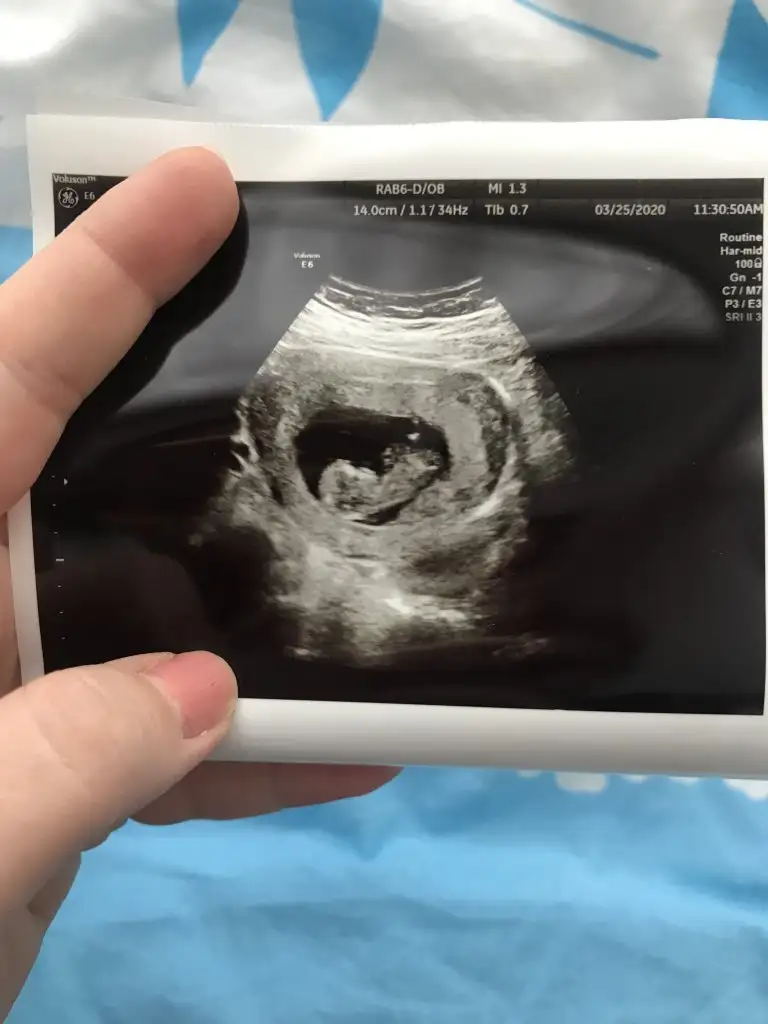

Her iki doktor farkli soyledi cinsiyetini 10ngun sonra kesin soyleriz dedi son fotograflar yeni bacak arasi net dikattli bakinca belki fikrin netlesir belki canimSanki erkek gibi 12 yada 13 hafta usgde paylaşın![]()

11 12 13 hafta usg olmalı burada 14 haftada nub oluşmuş oluyor sanki emin değilim erkek gibi gibi istediğim usg leride paylaşın14 haftalık tahmin edermisiniz

Evet burada daha önceki usg de nubu erkek gibi bacak arası usg göremedim buradaMerhaba biz 11 hafta olduk tahmin alabilirmiyim☺

10+5 burda Pazartesi kontrolüm var 12+1 olucaz inşallah atarım ozamanUsg net değil kaç hafta usg 12 13 de paylaşırsınız emin değilim sanki kız